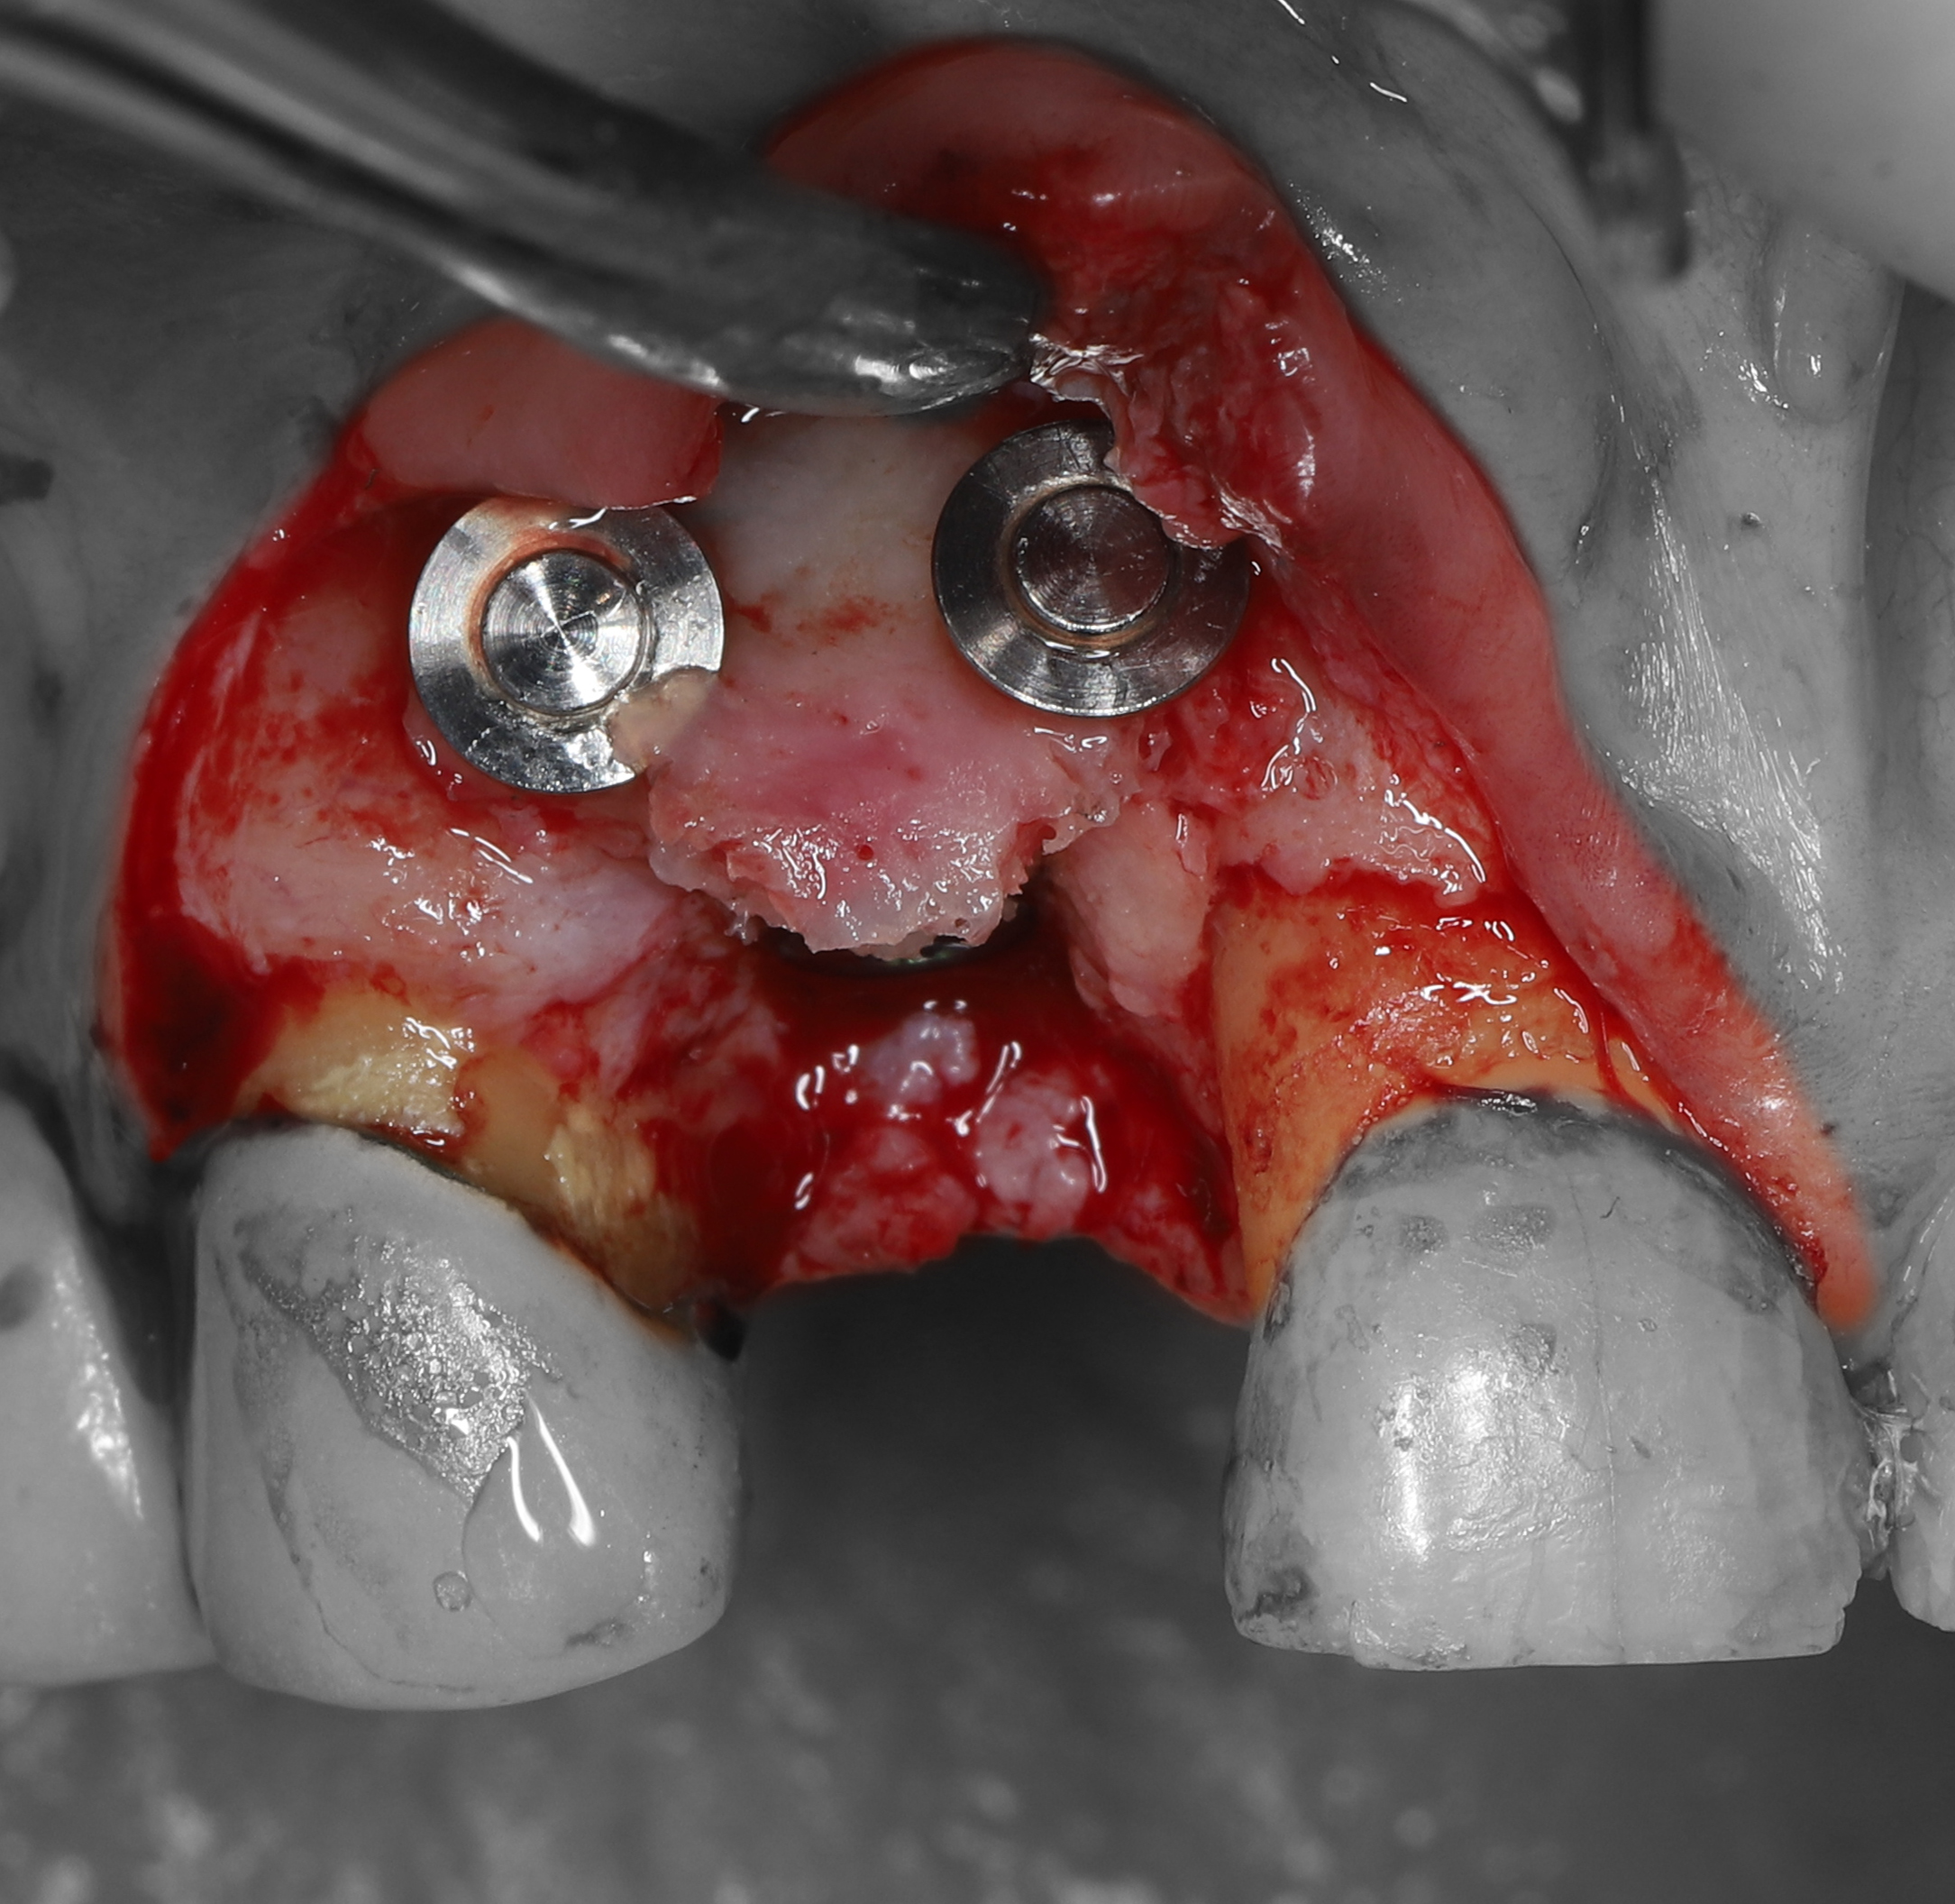

6) Костный графт был фиксирован в области вестибулярного дефекта с помощью прижатия 2-мя пинами.